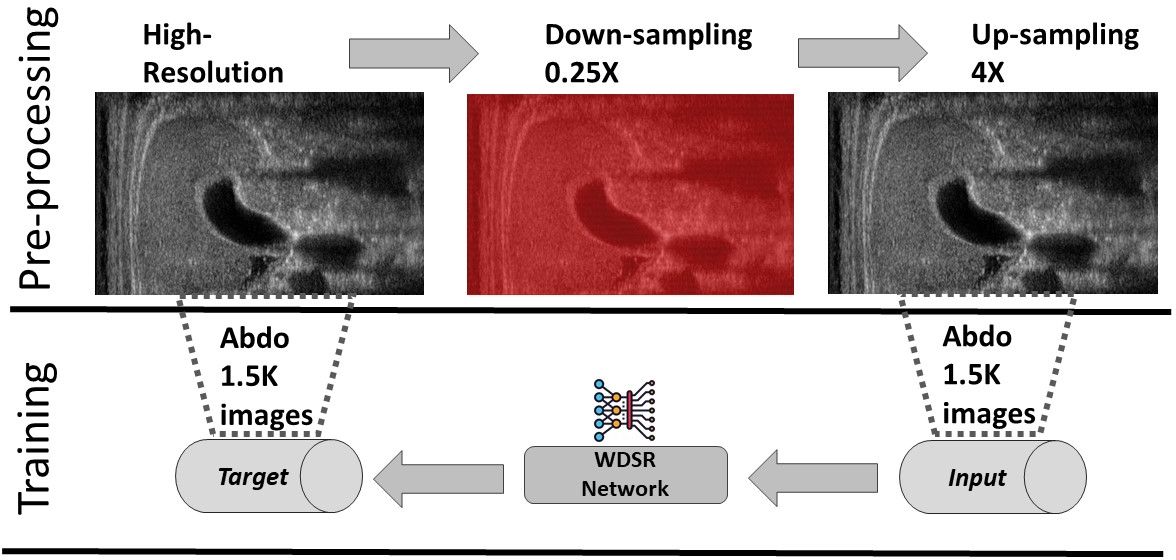

First, we compare several state-of-the-art up-sampling algorithms (Sect. 2) and identify the best method in terms of quantitative metrics and visual evaluation. Then, we train a neural network to improve the results of the up-sampling to match the target image (i.e., the high-resolution image). Our network does not perform the interpolation of the missing lines; in fact, this task is already performed by up-sampling. In contrast, our network learns how to transform the up-sampled lines into the target lines. To improve the quality of the up-sampling, we train multiple networks, each one specialised to the input anatomical district (e.g., cardiac, abdominal) and its low-resolution image (e.g., 0.5X, 0.25X). This specialisation improves the quality of the up-sampling since we specialise the network to a specific prediction. The execution time of the super-resolution depends on the up-sampling and the network prediction; the prediction is achieved in real-time on standard medical hardware. We summarise the proposed framework (Fig. 1), where we generate the data sets within the pre-processing phase, the learning-based models within the training phase, and the real-time super-resolution prediction within the test phase.

For the experimental part, we consider the Esaote data set, which contains more than 10K US images at different resolutions, and is acquired from different anatomical districts (e.g., obstetric, cardiac). Given a high-resolution image (i.e., the target) acquired by the probe, we build the corresponding low-resolution image by removing one line each 2 (0.5X) or 4 (0.25X). This approach is consistent with the acquisition of the US image, where the probe can acquire at the full, half, or a quarter of the maximum number of beamlines, depending on the activation of the piezoelectric crystals. We up-sample the low-resolution images through Cubic Convolution at 2X (applied to 0.5X low-resolution) or 4X (applied to 0.25X low-resolution). Then, we use the couples of up-sampled and target high-resolution images to analyse the proposed framework, through the training and the prediction of the learning-based network, with a specialisation in anatomic districts.

We generate a separate training data set of 1.5K images for each anatomical district and two different up-sampling resolutions of 2X and 4X. Then, the same images are denoised through a low-rank denoising algorithm [CP22] to build the training data set of 1.5K denoised images for each anatomical district. In total, we train 12 networks (i.e., 3 anatomical districts, 2 up-sampling factors, 2 (raw/denoised) images), each with 1.5K images as a training data set. In addition, for each anatomical district, up-sampling factor, and raw/denoised images we generate a validation data set of 400 images and a test data set of 200 images, using each image in only one of the three data sets.

We train each learning-based network (custom-WDSR) with 1.5K images, where the input is the outcome of the selected up-sampling method (i.e., Cubic convolution), and the target is the original high-resolution image. Indeed, input and target images have the same resolution, as the reconstruction of the missing lines has been already performed by Cubic convolution. Figs. 3, 4, and 5 show the results of the network prediction, compared with the input and the target images. Target images correspond to spatial high-resolution images; input images are the outcome of the up-sampling interpolation, which is applied to spatial low-resolution images (i.e., the down-sampling along the lateral direction of high-resolution images); prediction images represent the output of the neural network.